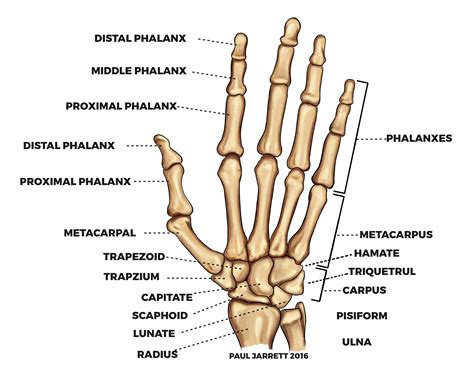

Detailed skeletal structure of the human hand and wrist

The anatomy of the hand wrist is built upon a complex arrangement of bones that allow for both stability and multi-axial movement. The wrist itself is comprised of the distal radius and ulna of the forearm, which articulate with the proximal row of carpal bones. There are eight carpal bones arranged in two rows, which act like a ball-bearing system to facilitate wrist flexion, extension, and rotation.

The structure of the hand bones is categorized as follows:

• Carpals: Eight small bones (scaphoid, lunate, triquetrum, pisiform, trapezium, trapezoid, capitate, hamate) located in the wrist.

• Metacarpals: Five long bones that form the palm of the hand.

• Phalanges: The 14 bones that make up the fingers and thumb; the thumb has two phalanges, while each finger has three.